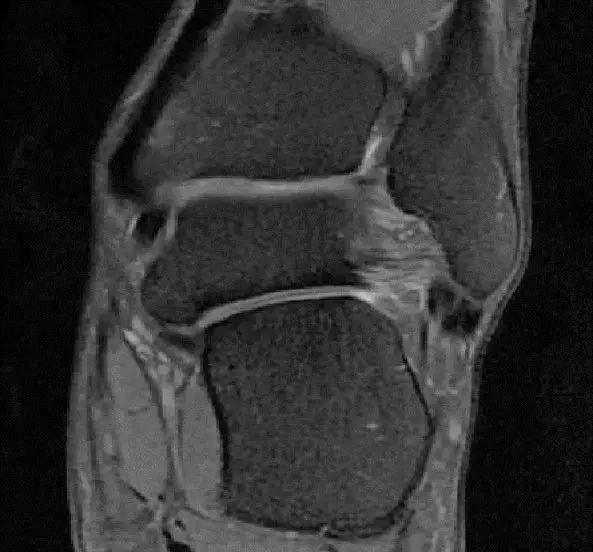

从这张片子我们可以看到正常的韧带结构,包括距腓前韧带,跟绯韧带,它是质地比较均一,T2相高信号,连续性良好,并且有良好的张力,从冠状位也可以看到跟绯韧带,在腓骨肌腱的深方,也是T2相跟T1相的低信号,有良好的连续性,张力也不错。